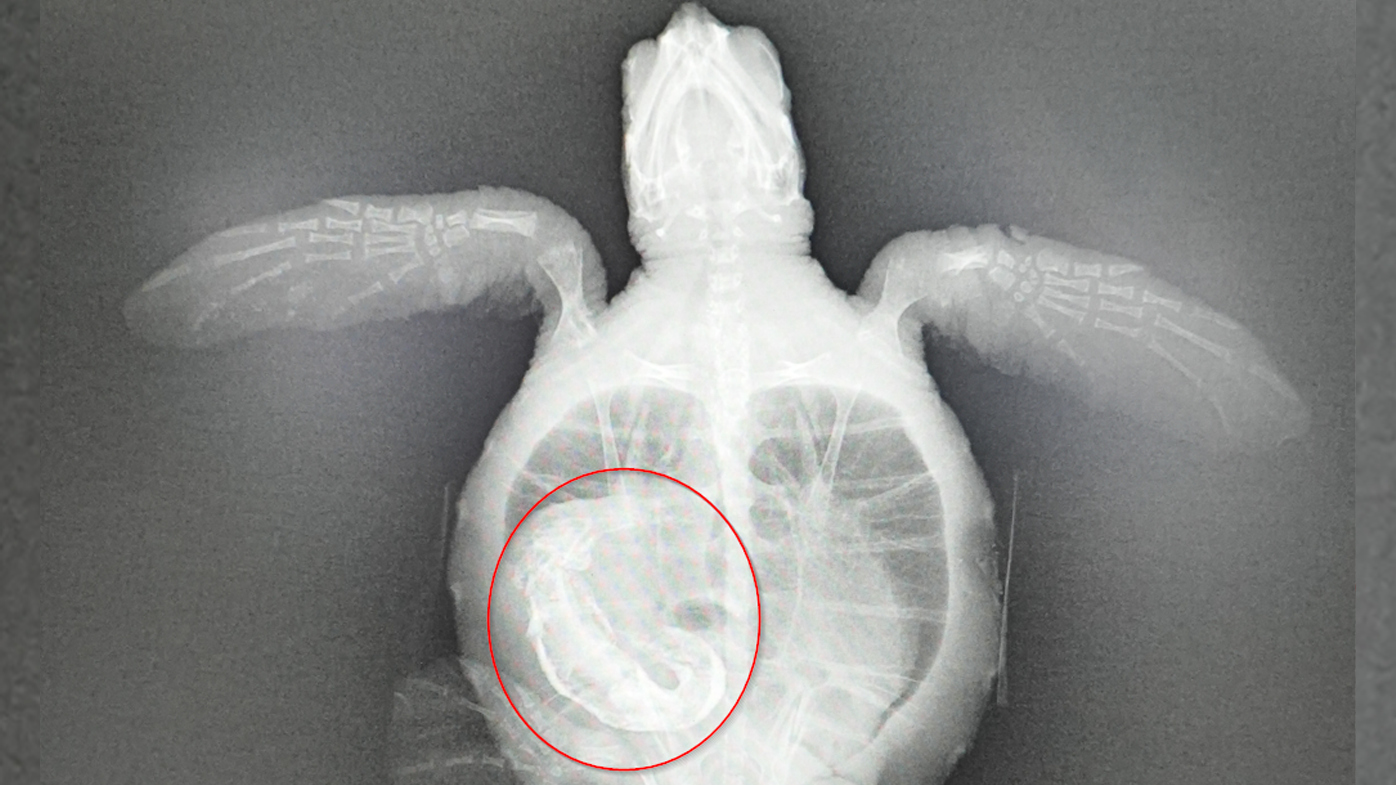

Wildlife carers were horrified to find plastic already in its stomach following an X-ray

An x-ray showed a substantial blockage in the colon of the green sea turtle.

Large pieces of plastic had to be removed by hand from the turtle's digestive tract.